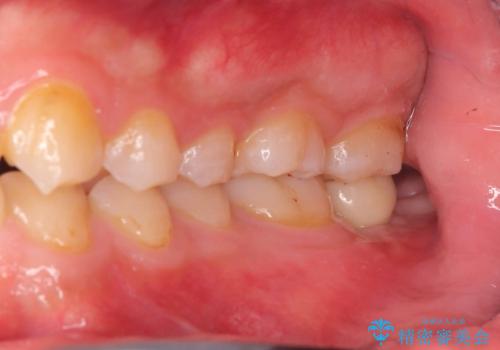

CRの劣化による虫歯|虫歯治療|セラミッククラウン|審美回復|神経を残す治療

担当医 河野豊嘉